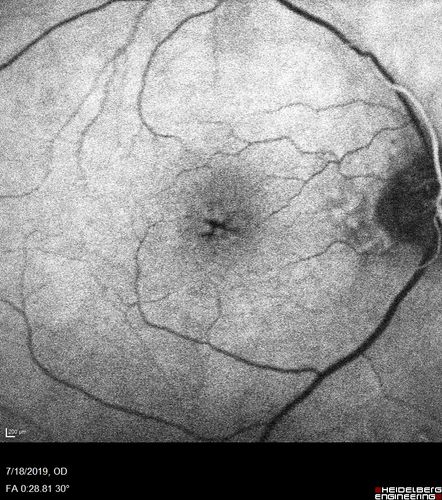

Stellate non-hereditary idiopathic foveomacular retinoschisis (SNIFR) and optic nerve drusen

84 year old man No visual complaints. Not diabetic, cataract surgery 8 years ago. Meds: Omeprazole, Tamsulosin (Flomax)

VA 20/32 OD, 20/20 OS